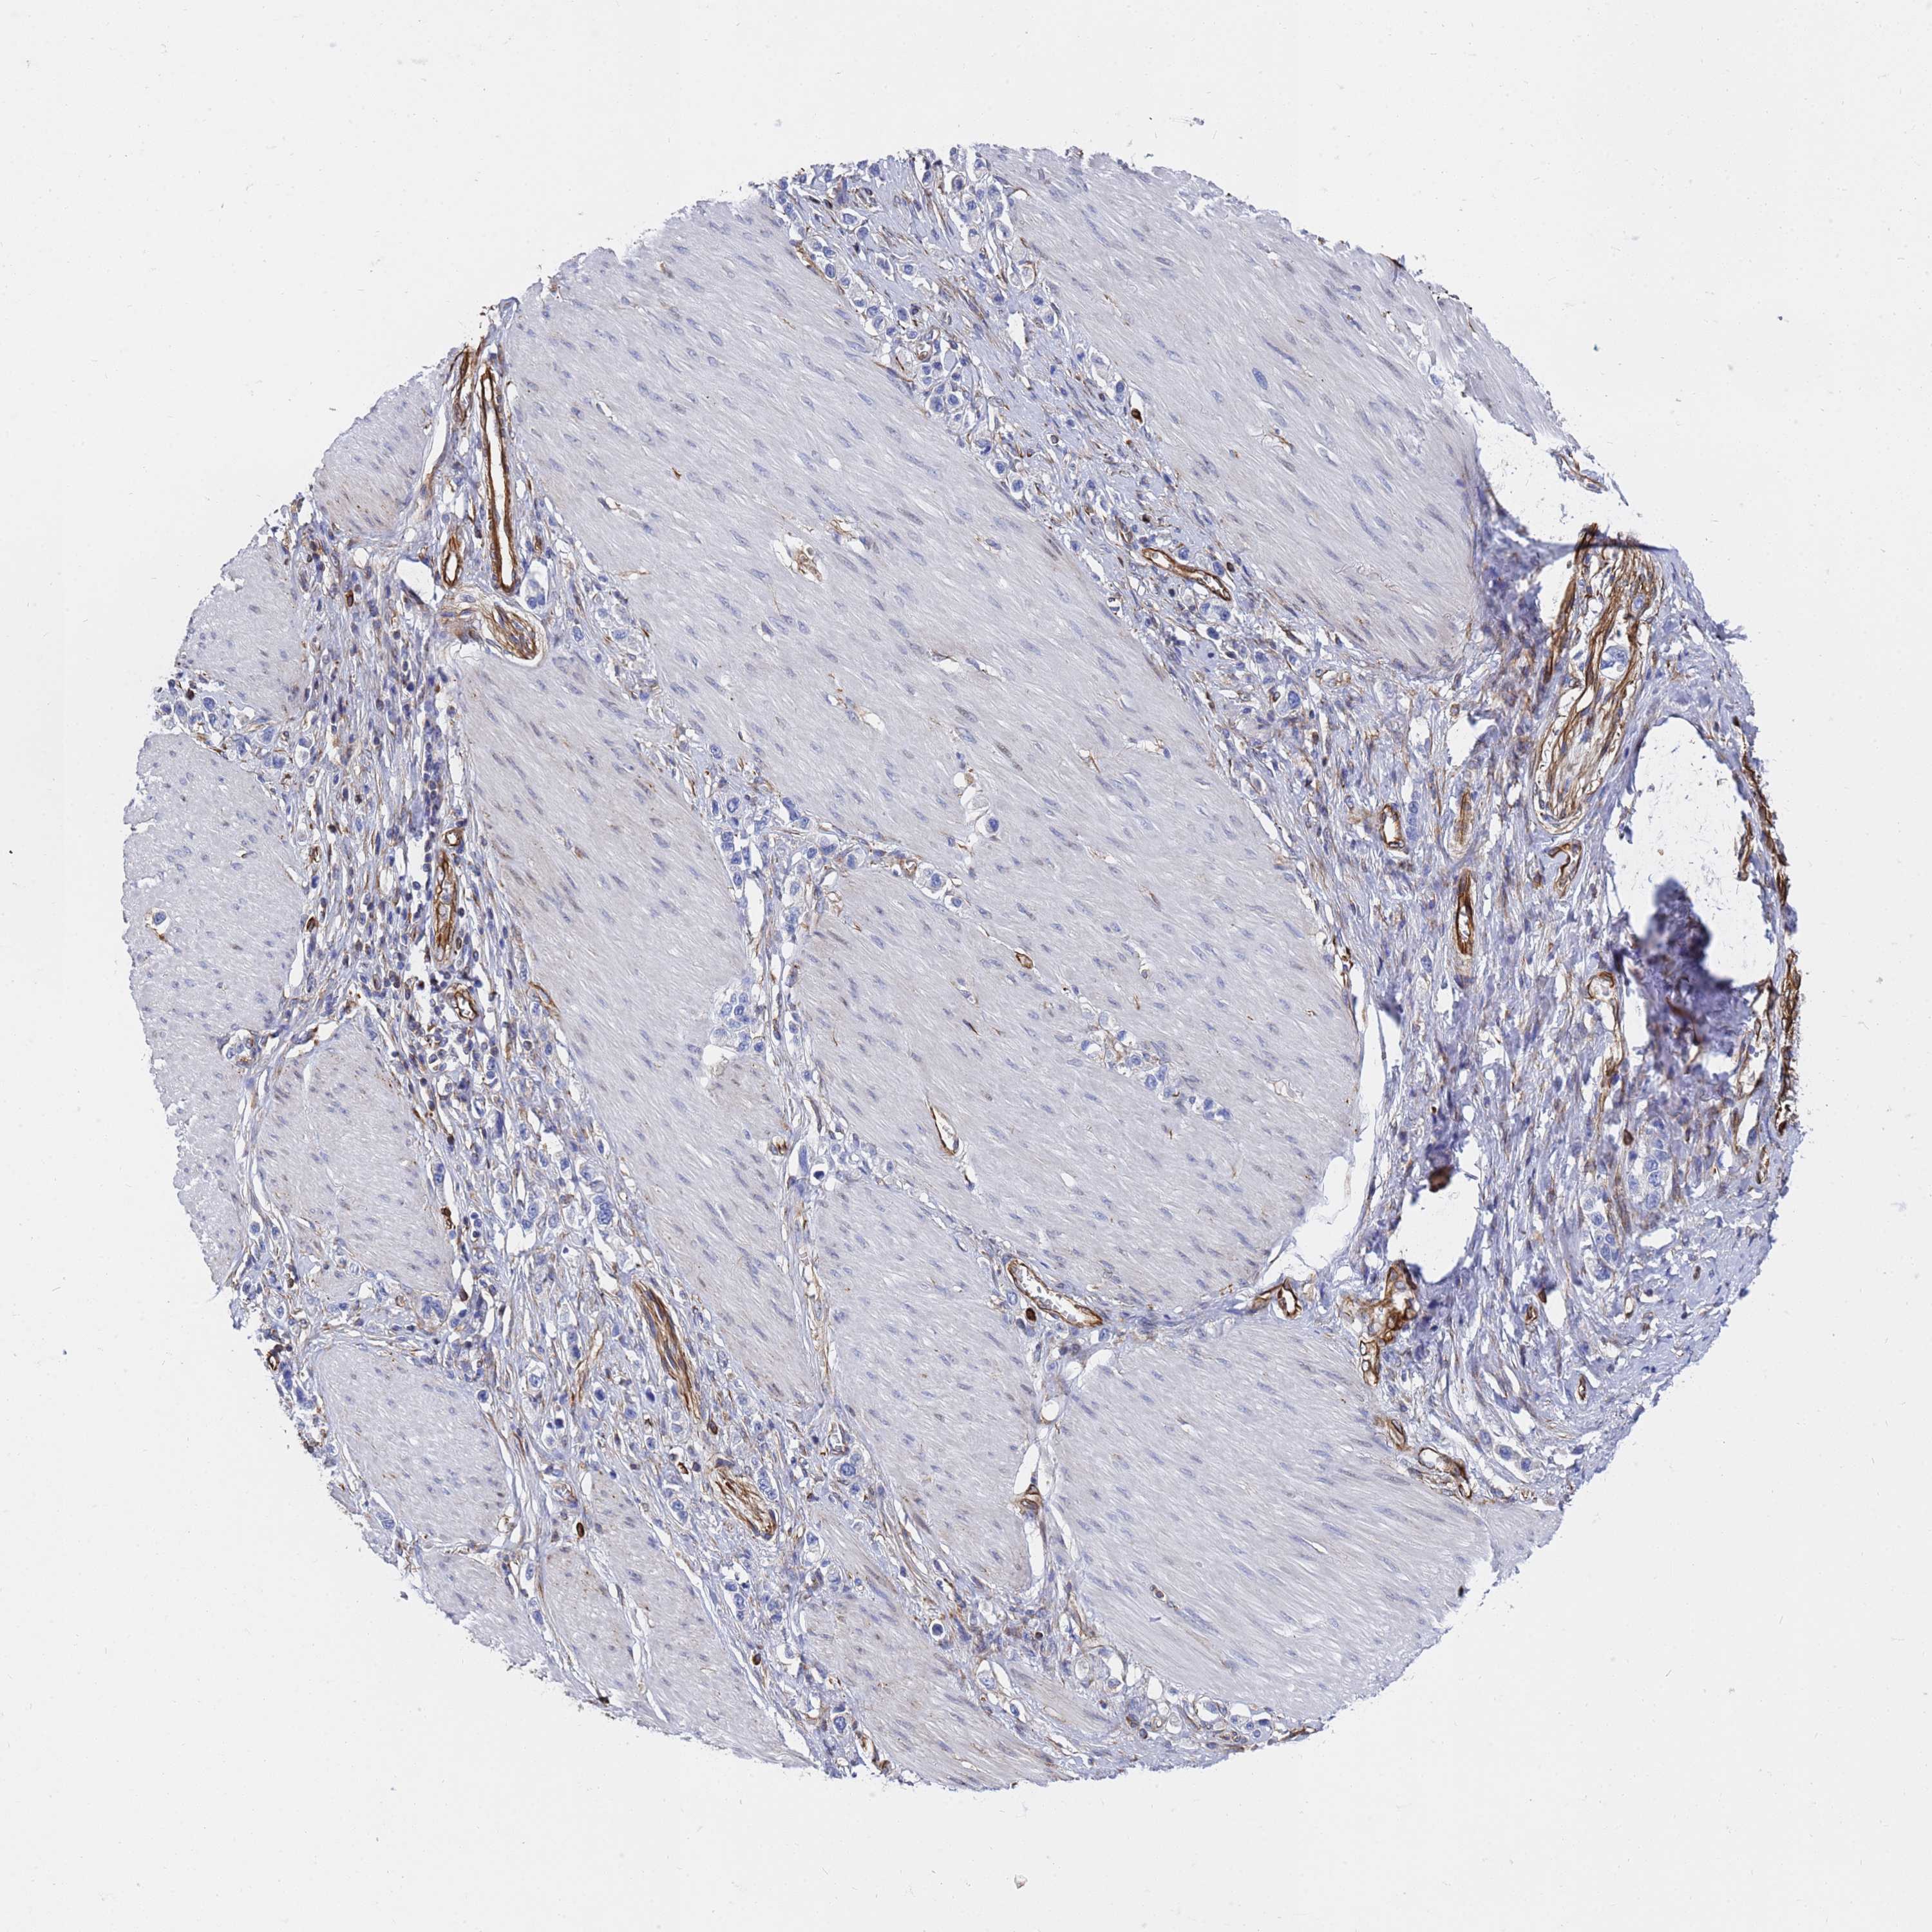

STOMACH CANCER - Protein expressioni

A mouse-over function shows sample information and annotation data. Click on an image to view it in a full screen mode. Samples can be filtered based on level of antibody staining by selecting one or several of the following categories: high, medium, low and not detected. The assay and annotation is described here.

Note that samples used for immunohistochemistry by the Human Protein Atlas do not correspond to samples in the TCGA dataset.

Antibody stainingi

Antibody staining in the annotated cell types in the current human tissue is reported as not detected, low, medium, or high, based on conventional immunohistochemistry profiling in selected tissues. This score is based on the combination of the staining intensity and fraction of stained cells.

Each image is clickable and will lead to virtual microscopy that enables deeper exploration of all samples and also displays staining intensity scores, fraction scores and subcellular localization as well as patient and tissue information for each sample.

Antibody HPA046224

Staining

High

Medium

Low

Not detected

Intensity

Strong

Moderate

Weak

Negative

Quantity

>75%

75%-25%

<25%

None

Location

Nuclear

Cytoplasmic/membranous

Cytoplasmic/membranous,nuclear

Adenocarcinoma, NOS